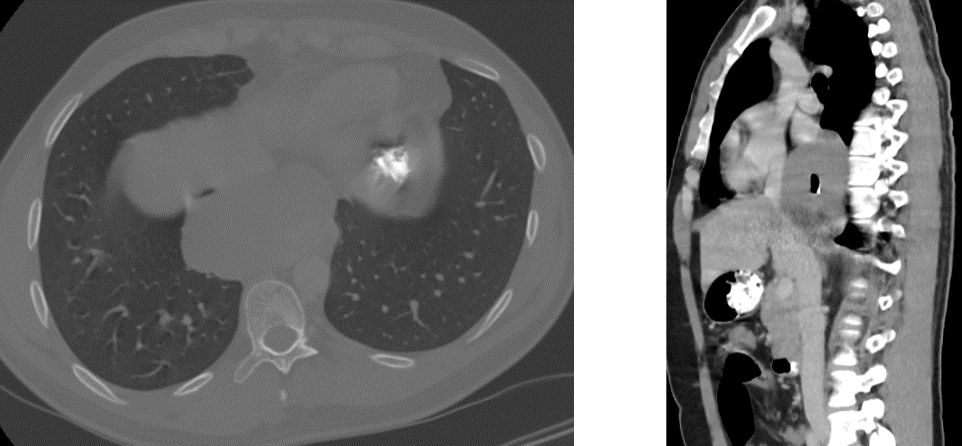

Patient de 35 ans, Pyrosis depuis plusieurs mois.

Pas d'amaigrissement

Patient non fumeur, non OH - non Tabac dépendant Examen clinique négatif. Pas d’ADP de Virchow Troisier.